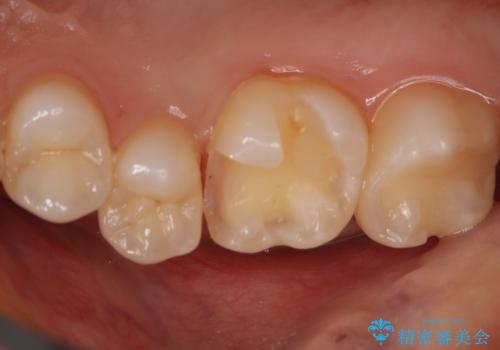

- 右上6番の保険材料で詰められた部分をセラミックにやり変え希望の患者様です。

切削量などを考慮し、セラミックインレーでの治療を選択しました。

う蝕が深くまで進行していたので、全て除去した上でCR裏層を行い形成、印象を行っています。